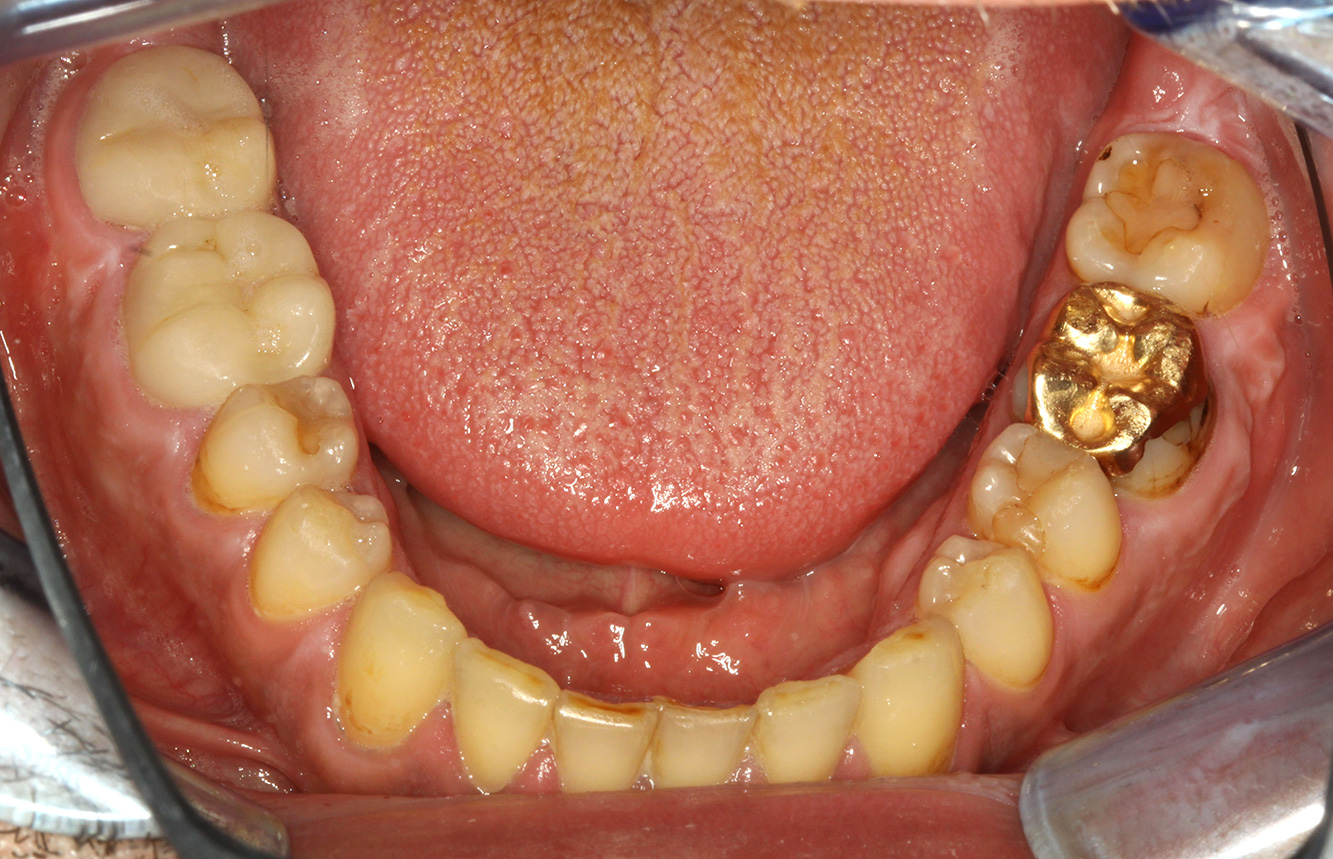

In the medical history, the 55-year-old patient states that he has no systemic disease and is not taking any medication. The patient’s lifestyle is similarly unremarkable. The patient has a few tooth restorations and two implants (2nd and 4th quadrants). On the basis of current findings, gingivitis is identified in an otherwise stable periodontal condition on the reduced periodontium (stage III, grade A). more

The healthy patient with pre-existing periodontal disease & peri-implantitis

A 52-year-old patient presents at a preventive care session. The patient has no systemic disease and is not taking any medication. He has had various dental treatments and also has two active carious lesions. In addition, the patient has four implants (2nd, 3rd and 4th quadrants). He is revealed to have early periodontal disease (stage IV, grade B). His periodontal condition is stable; a probing depth of Probing depths (ST) of 5 mm is only evident at the implant in region 36. Gingivitis is also identified. more